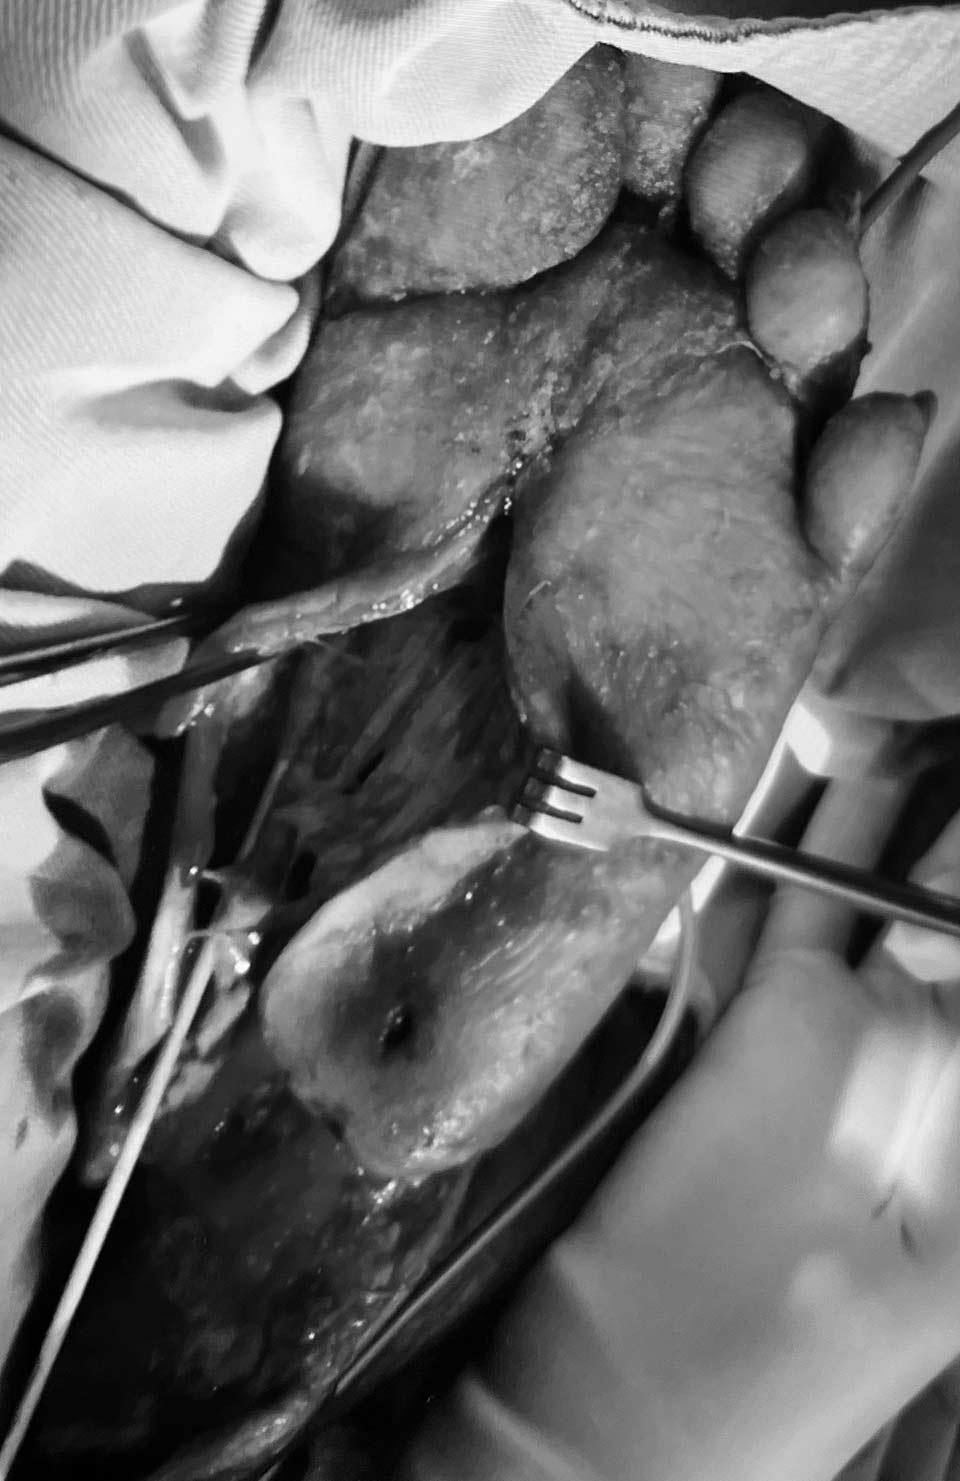

打通血管之後,我們把足底的空腔打開,腐敗的肌腱切除。